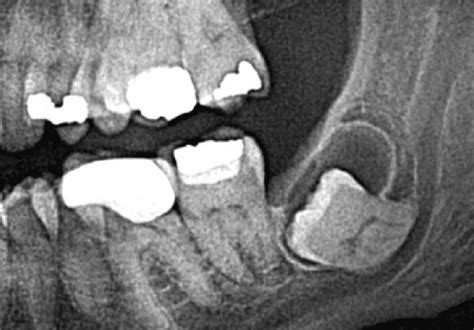

Ante la presencia de los síntomas antes descritos, se debe recurrir a un profesional de la salud dental para que determine cuál es el diagnóstico correcto. Generalmente los quistes dentales se observan a través de una radiografía panorámica o una radiografía 3D que es mucho más precisa y exacta.

Estos estudios determinarán el tamaño del quiste, su origen, la posición, el estado del diente y de la encía y cómo afecta a los dientes cercanos a él. En base a esto se puede establecer la manera de extirpar el quiste que será diferente en cada caso.

- Dentígero: Este quiste se produce alrededor de dientes no erupcionados como muelas del juicio que aún no han salido y provoca la pérdida ósea a su alrededor.